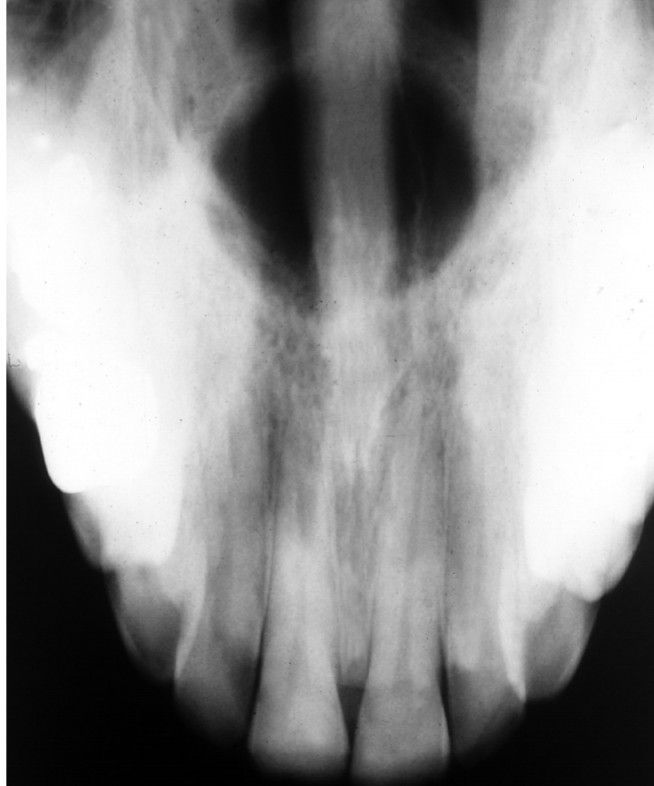

Median palatal cyst

Occlusal radiograph of same patient depicted. A well-circumscribed midline radiolucent defect can be seen, which is separate